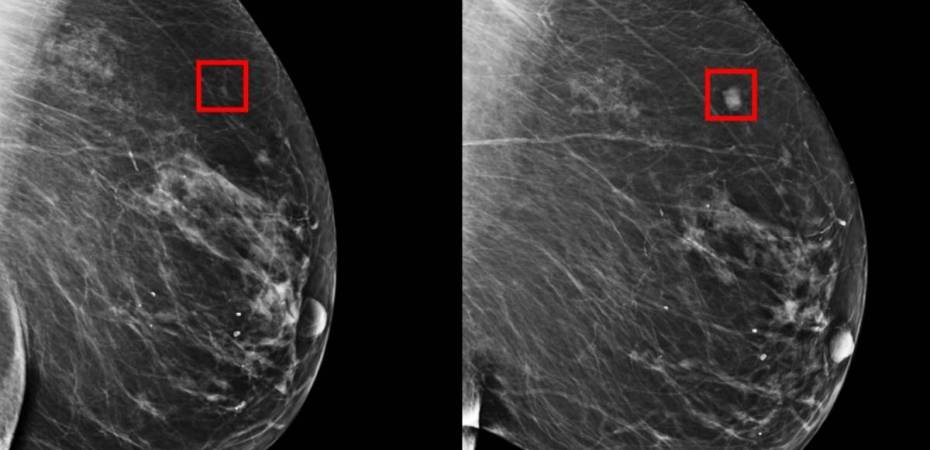

El Laboratorio de Inteligencia Artificial y Computación del MIT creó un modelo de predicción que detecta tempranamente el cáncer de mamas.

El MIT a través de su Laboratorio de Inteligencia Artificial y Computación, creó una AI impresionante que logra detectar hasta con cinco años de anticipación el cáncer de mamas.

Entrenado en mamografías y resultados conocidos de más de 60,000 pacientes con MGH, el modelo aprendió los patrones sutiles en el tejido mamario que son precursores de tumores malignos, sostiene el MIT.